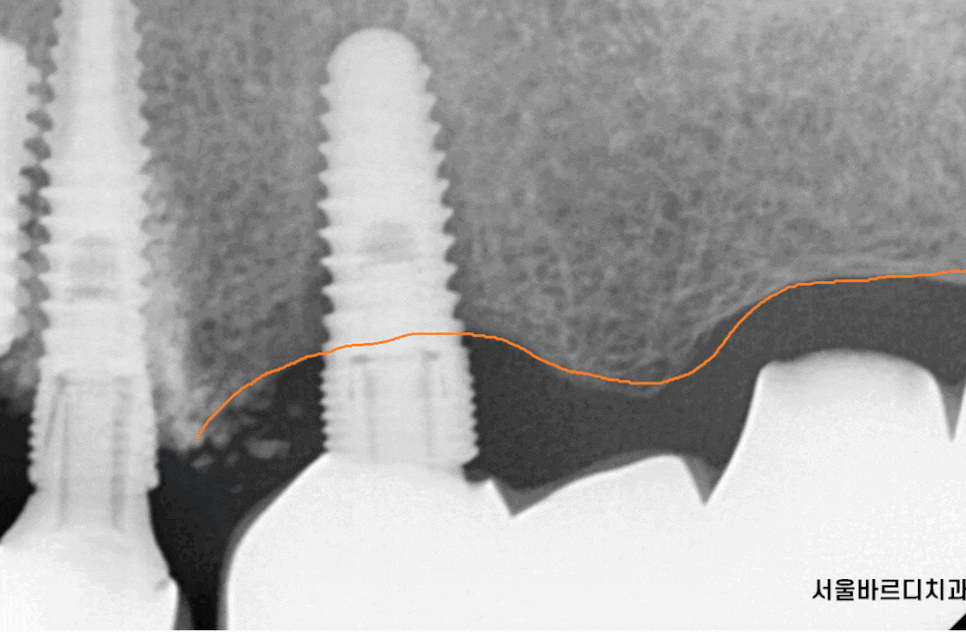

23.06.15

심어둔 임플란트 뼈 높이가

점점 내려가

임플란트가 덜렁덜렁 거리고